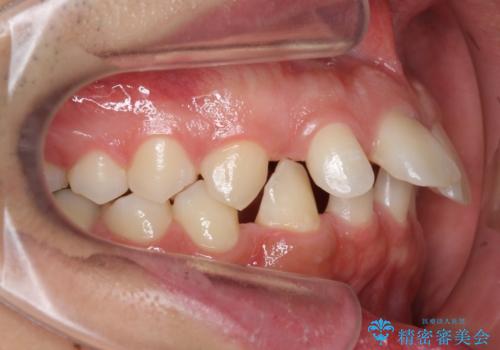

生え変わり自体は問題なかったため経過観察しています。

永久歯の前歯が生えてきた際、顎と歯の大きさの不調和がない限り、生え変わりに伴ってたいていの隙間は自然に閉じます。

しかし、中には上唇小帯の高位付着が原因で隙間が残ってしまったり、矯正治療で閉じても再度開きやすい方がいらっしゃいます。